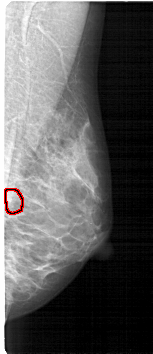

A_1272_1.RIGHT_MLO

RIGHT_MLO LINES 5296 PIXELS_PER_LINE 2281 BITS_PER_PIXEL 12 RESOLUTION 43.5 OVERLAY

FILE: A_1272_1.RIGHT_MLO.OVERLAY

TOTAL_ABNORMALITIES 1

ABNORMALITY 1

LESION_TYPE CALCIFICATION TYPE PLEOMORPHIC DISTRIBUTION CLUSTERED

ASSESSMENT 4

SUBTLETY 3

PATHOLOGY BENIGN

TOTAL_OUTLINES 1

BOUNDARY